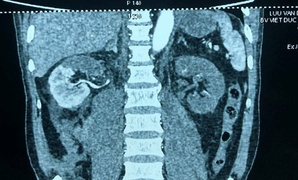

Đầu tháng 9/2020, bệnh nhân bị viêm phúc mạc do hoại tử gần như toàn bộ ruột non. Bệnh nhân được Bệnh viện huyện Than Uyên (Lai Châu) phẫu thuật cấp cứu cắt gần hoàn toàn ruột non (chiều dài ruột non hiện tại của bệnh nhân chỉ còn 20cm).

Ngày 29/9, bệnh nhân được chuyển về điều trị tại Bệnh viện Quân y với chẩn đoán suy mòn, suy kiệt do hội chứng ruột cực ngắn type 3.

Bệnh nhân được điều trị tích cực, nuôi dưỡng qua đường tĩnh mạch. Sau đó người bệnh xuất hiện gan chuyển hóa liên quan tới hội chứng suy chức năng ruột.